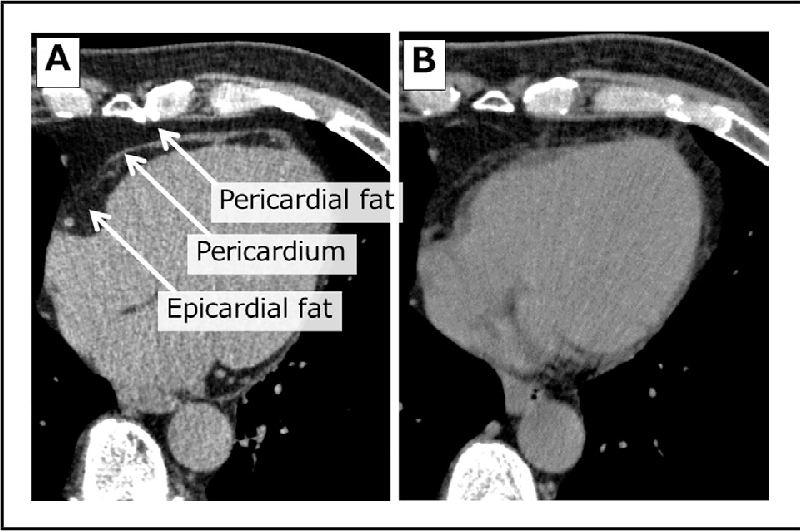

The misleading concept of the similarity between epicardial fat and pericardial fat is tedious. Anatomically, the difference between epicardial and pericardial fat is obvious. There are two locations of epicardial fat, one is the external wall of the myocardium and the other is the pericardium layer.

Now when we talk about the pericardial fat, it is located on the anterior of epicardial fat. The location of the fat is between the visceral and parietal layers. The epicardial fat is much closer to the myocardium and most importantly they both share the same blood supply.

There is an abundance of adipokines in epicardial fat. Pericardial fat, on the other hand, is the opposite. However, the modulation of coronary arteries is pericardial fat. The epicardial and pericardial fat is different from a clinical and anatomical perspective. The thickness of epicardial and pericardial fat varies largely.